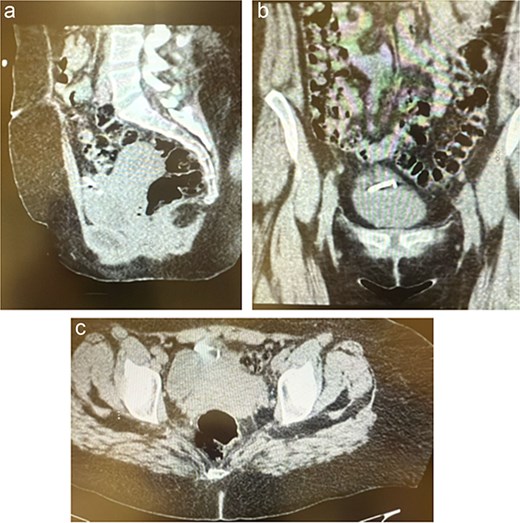

After 72 h of antibiotic therapy and clinical stabilization, she underwent a diagnostic laparoscopy. Intraoperative findings confirmed uterine perforation with the IUD partially embedded in the anterior abdominal wall amidst dense inflammatory adhesions and a localized abscess cavity. The IUD was carefully dissected free and removed. The abscess cavity was irrigated and drained thoroughly (Fig. 3).

Demonstrates the intraoperative findings during diagnostic laparoscopy. The IUD is visualized embedded in the anterior abdominal wall, surrounded by inflamed tissue consistent with a localized abscess. This confirms the diagnosis of uterine perforation and extrauterine migration of the IUD.